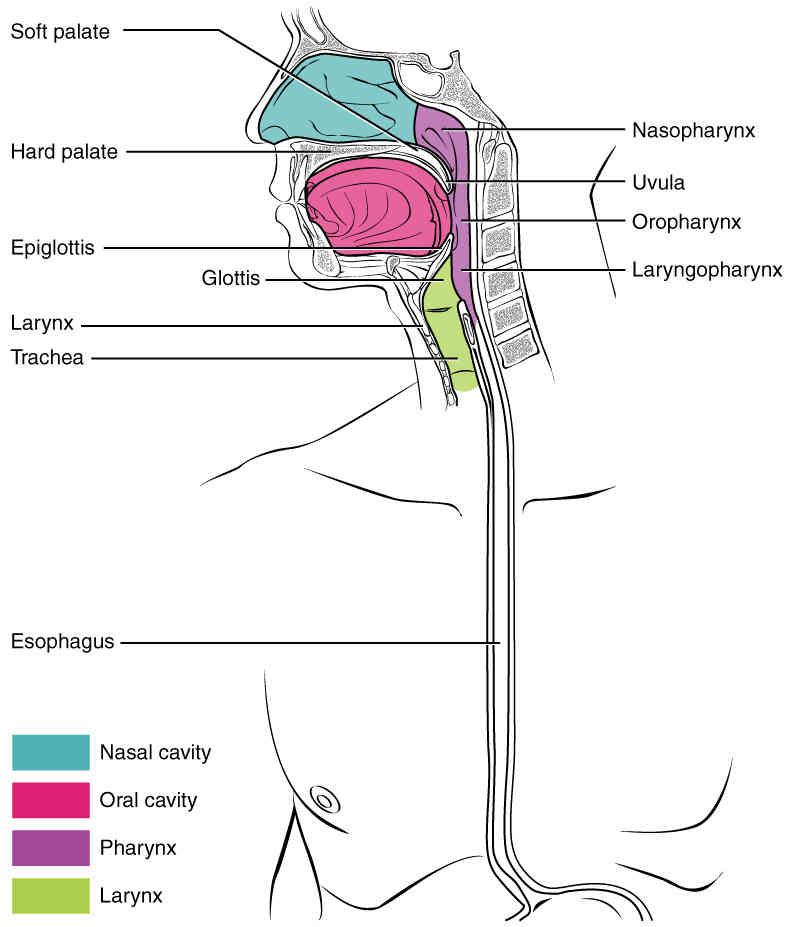

This page is under construction. For now, it is just a resource of the images found in the OpenStax Anatomy and Physiology Handbook. It wil slowly change into a revision tool. Each slide has a number. Use this to refer to the slide. When completed, it will have an unlabelled section, with labelled slides in parallel. On the unlabelled slides, write your answer and use the labelled slide to assess yourself. Keep track by also noting the number on each slide. Improvement at each attempt is important, more so than full marks on a first attempt.